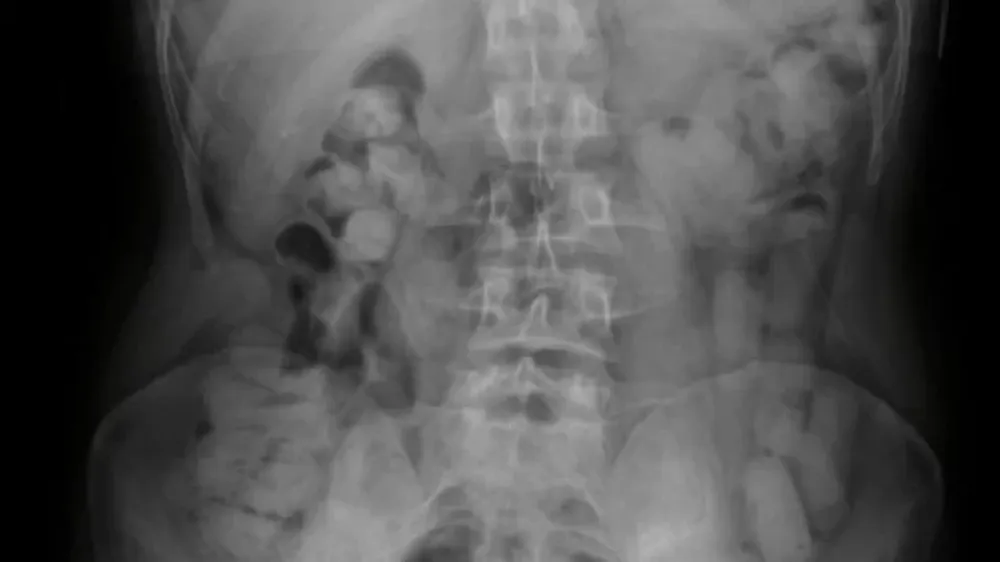

Ante la presunción de estar frente a un hecho ilícito, los uniformados tomaron contacto con el Juzgado Federal de Tucumán, el cual autorizó el traslado de los ciudadanos hacia el nosocomio local, a los fines de efectuar las placas radiográficas.

Los resultados de los estudios médicos confirmaron la presencia de cuerpos extraños en el interior de los estómagos de los pasajeros, quienes inmediatamente quedaron bajo observación.